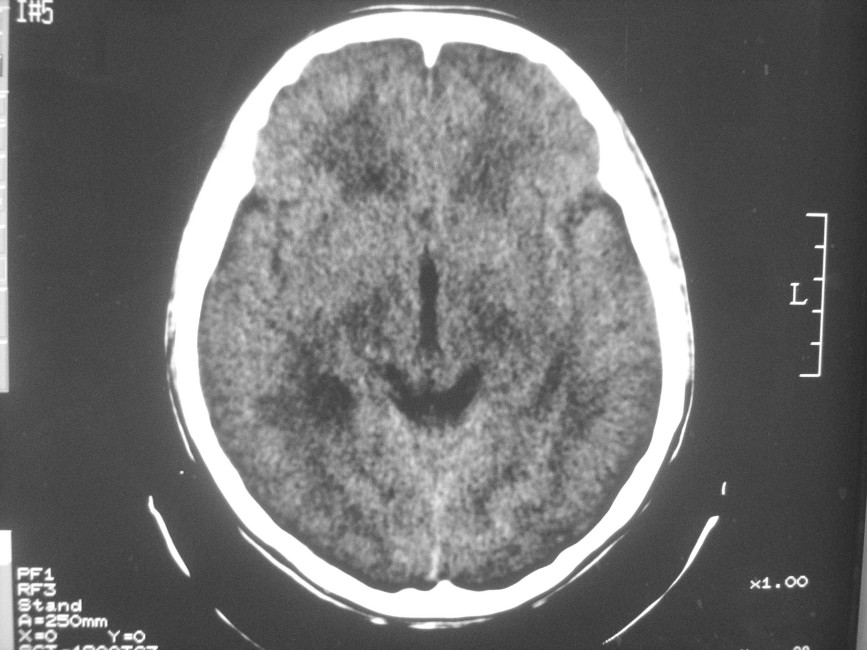

以下是引用zzyy在2008-6-16 10:13:00的发言:[br]两侧脑白质呈对称性密度减低,病儿有发热及脑膜刺激征。考虑急性病毒性脑炎。